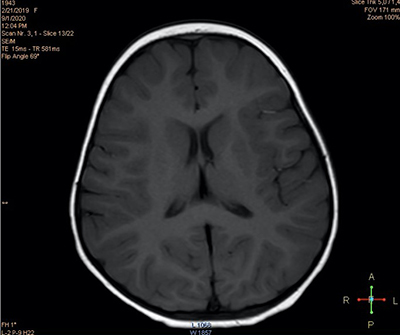

При проведении нейровизуализационного исследования (МРТ 2 Тл) выявлены признаки некоторого усиления МР-сигнала в парагиппокампальной области (см. рис. 2а) и незначительного расширения переднего субарахноидального пространства (см. рис. 2б), что может свидетельствовать в пользу перенесенной гипоксически-ишемической перинатальной энцефалопат На третьи сутки количество эпизодов отведения глаз сократилось до 6, при этом их продолжительность не превышала нескольких секунд.

Инструментально-диагностические и лабораторные исследования чаще всего демонстрируют нормальные показатели нейровизуализации, электроэнцефалографии и метаболических параметров крови и ликвора у детей с идиопатическими (генетическими) формами заболевания. Золотой стандарт нейровизуализационного обследования — МРТ головного мозга, как правило, не выявляет патологических изменений.